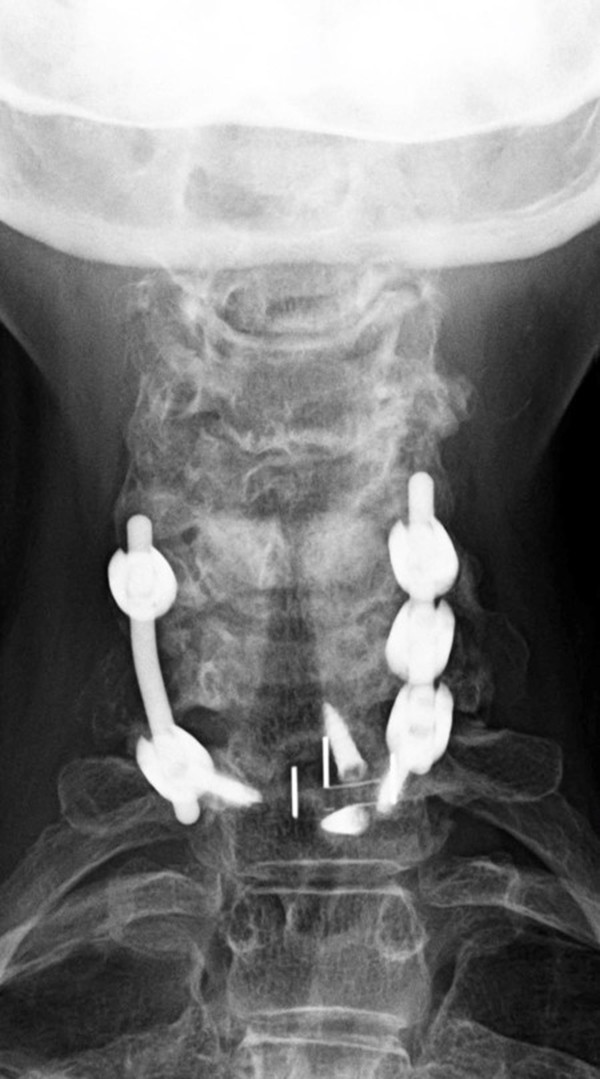

Odontoid screw (nail) fracture fixation with posterior cervical fixation plates and screws |

| There is also an anterior cervical fusion plate and screws from C3-6. |

Patient with rheumatoid arthritis and atlantoaxial (C1-C2) subluxation and generalized cervical spine laxity |